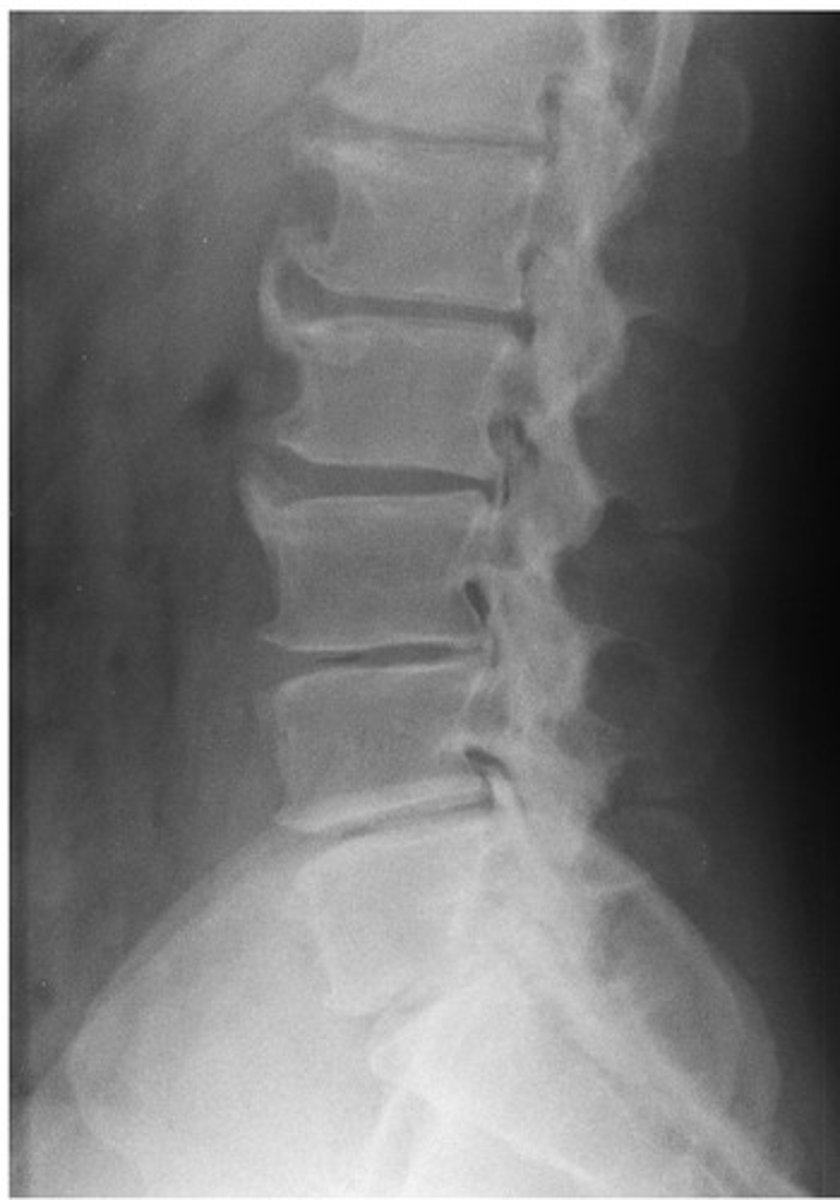

What diagnosis is this?

Non-marginal enthesophytes

Psoriatic Arthritis (PsA)